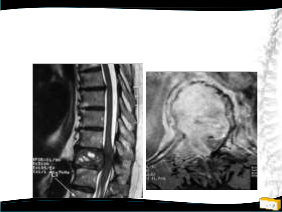

OLGU

• 40y, K

• Meme Ca

• Enstrumante edilmiş

• 3/5 paraparetik geldi

• RT aldı, 18 aylık takipte sorunsuz